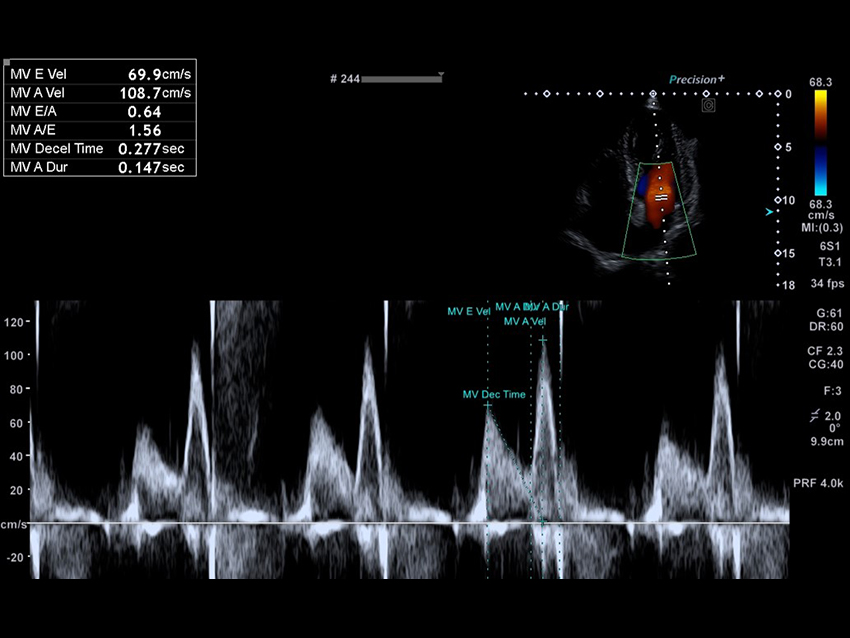

Aplio beyond tích hợp các công cụ AI thông minh hỗ trợ nhận diện cấu trúc giải phẫu, tự động đo lường và phân tích, giúp rút ngắn thời gian thực hiện thủ thuật, nâng cao độ nhất quán và tin cậy kết quả cho bác sĩ. Các thuật toán tự động giúp xác định vị trí cấu trúc, hỗ trợ trong các ứng dụng phức tạp và nâng cao hiệu quả quy trình làm việc.